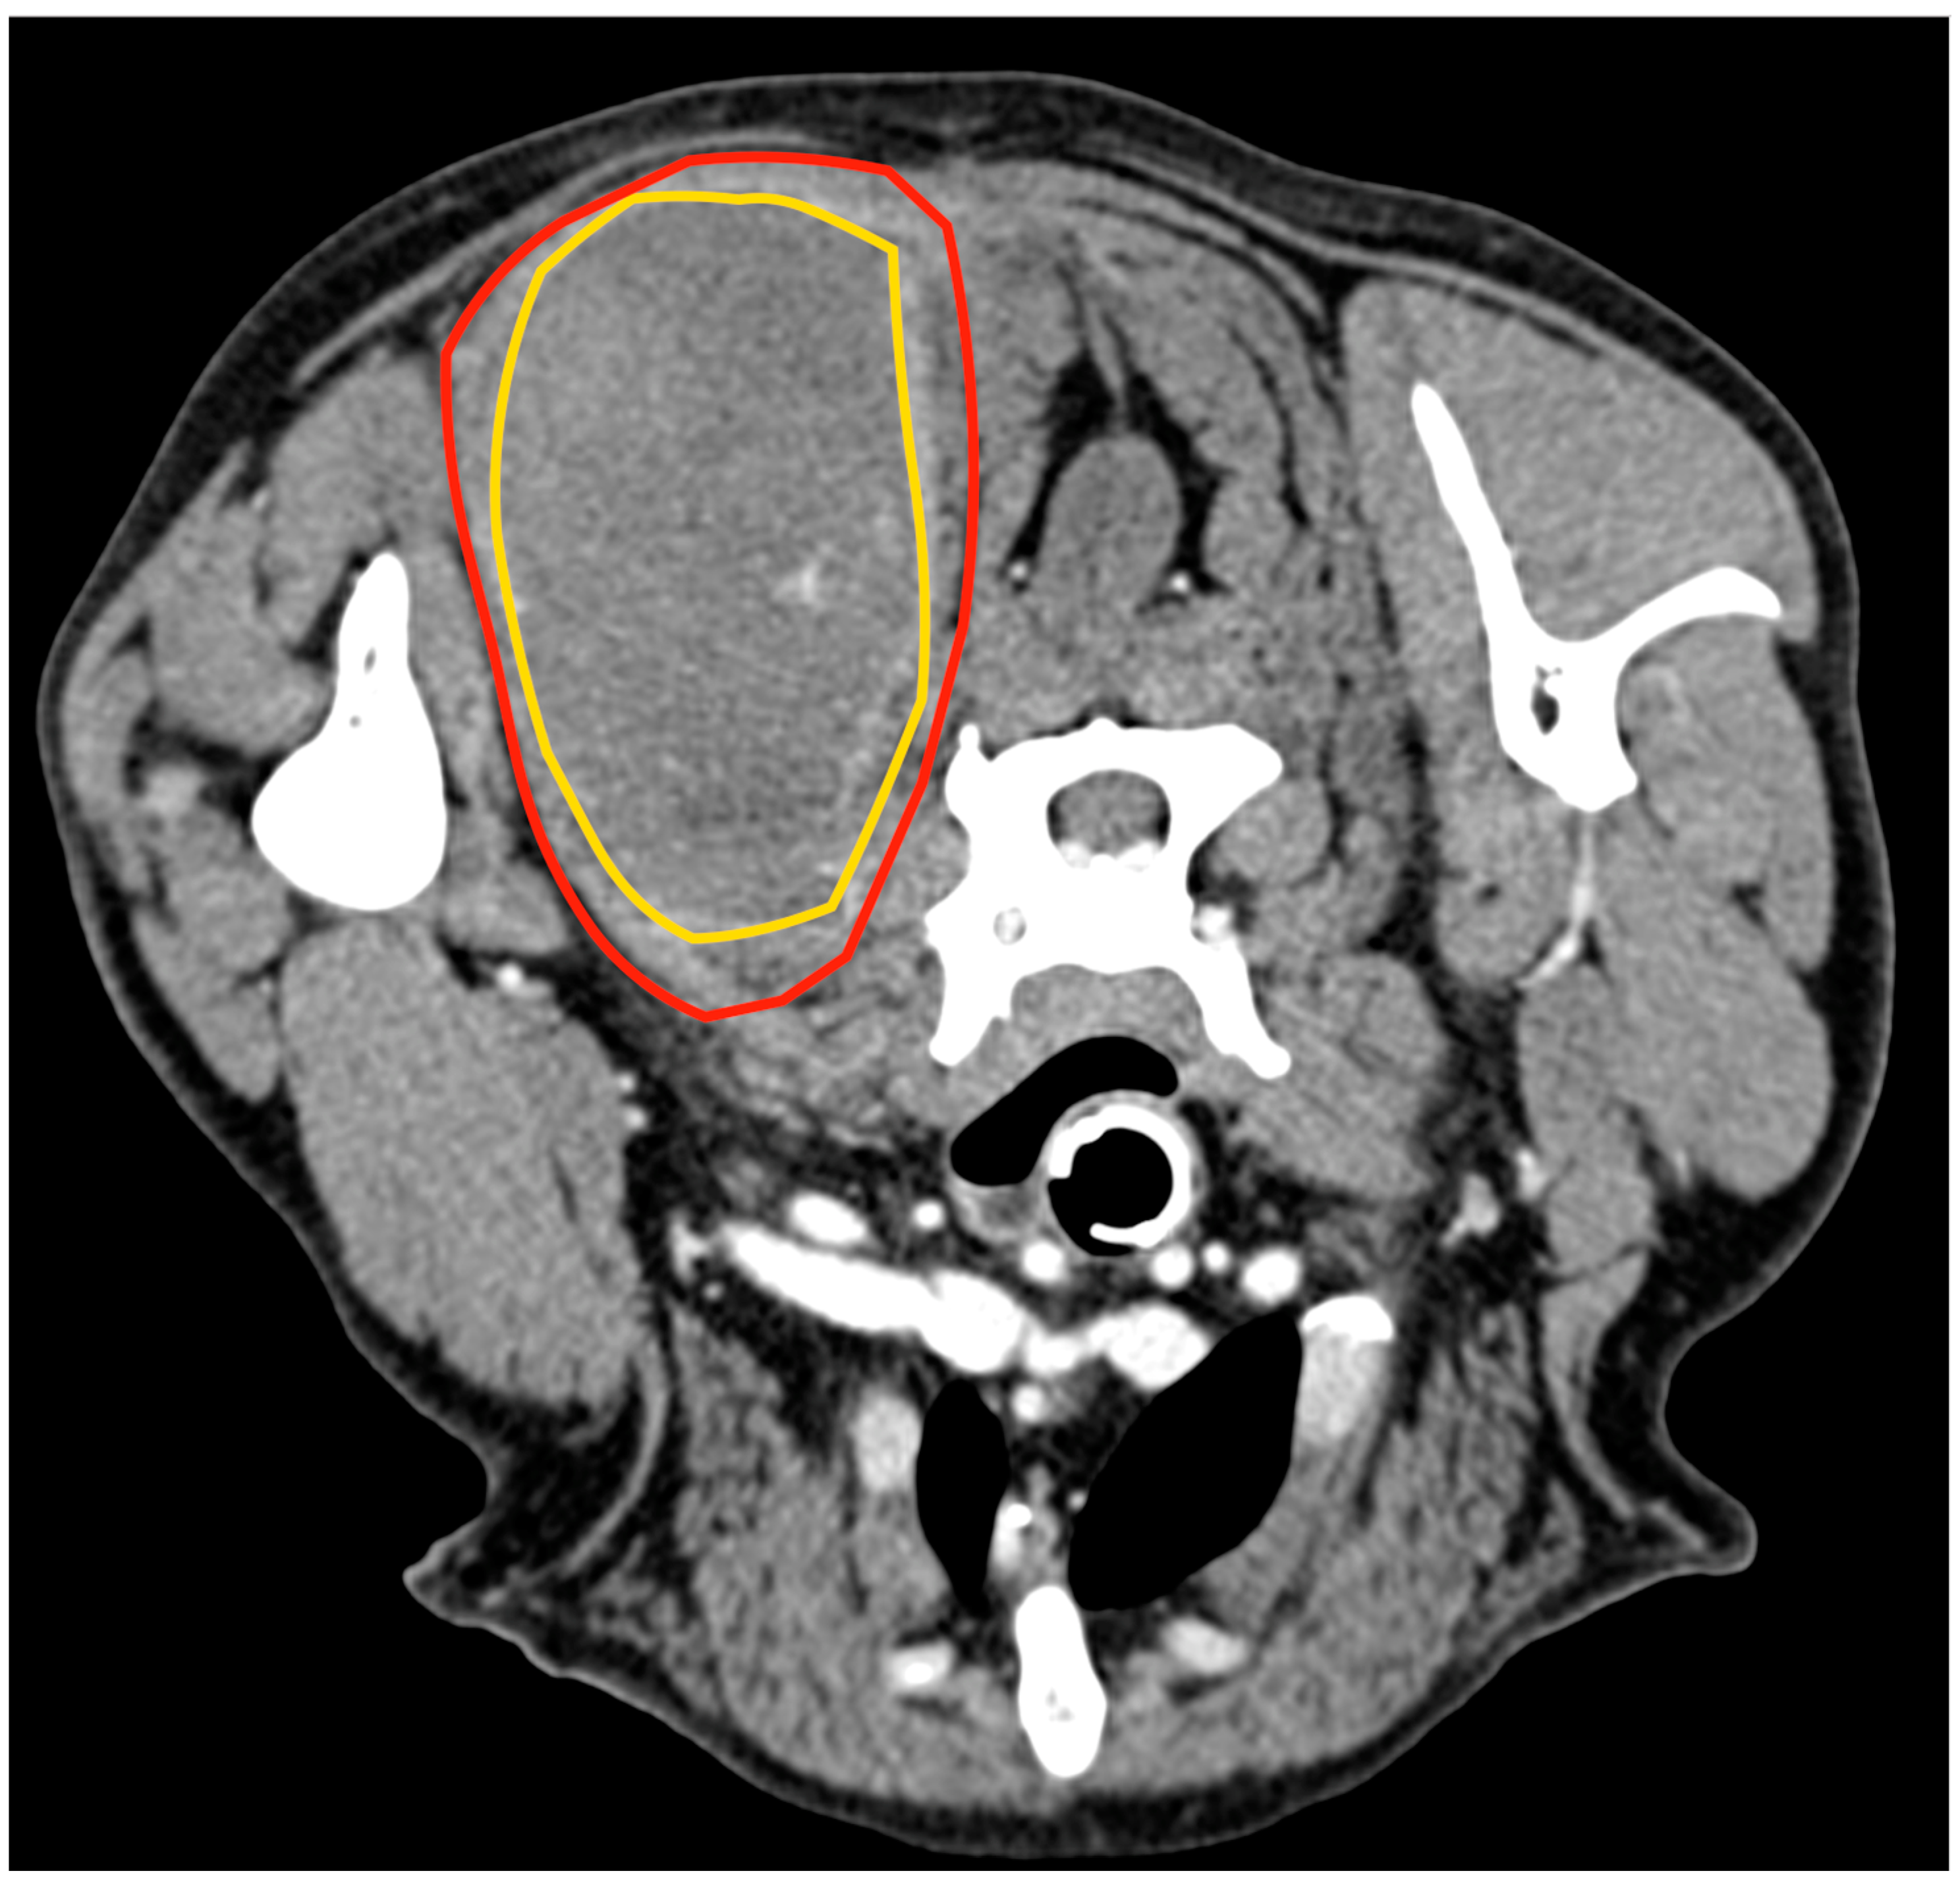

Cytology of the lesion via fine needle aspiration (FNA) was not diagnostic; therefore, an incisional biopsy was performed at the time of the total body CT. This revealed a 5.8 cm × 5.5 cm, poorly defined mass confined within the biceps femoris muscle, with heterogeneous enhancement after the administration of an intravenous contrast medium (Figure 2). No lesions suggestive of metastatic spread were observed. The histology from the bioptic sample was morphologically suggestive of PWT.

Figure 2.

Tomographic appearance of the sarcoma within the biceps femoris muscle, axial view (A). The yellow line delimitates the tumours, the red line the biceps muscle 3D reconstruction, and the white arrow indicates the tumour (B).

3.3. Case 3

An 8-year-old 35 kg spayed female mixed breed was referred for a 10 cm mass localised between the dorsal neck and the left scapular region, which had been noted a week earlier and had grown rapidly. At clinical examination, the mass appeared as a painful, firm, subcutaneous lesion adhering to the underlying tissues. No regional lymphadenopathy was detected. The cytology performed by the referring veterinarian was indicative of a malignant mesenchymal sarcoma. Total body CT confirmed the anatomic confinement of the tumour to the dorsal surface of the splenius capitis (Figure 5). No other anomalies were found based on the CT exam.

Figure 5.

Tomographic appearance of the neoplasm within the splenius capitis muscle between the seventh cervical vertebra and the medial surface of the scapula. The yellow line delimitates the tumours, and the red line is the splenius capitis muscle.